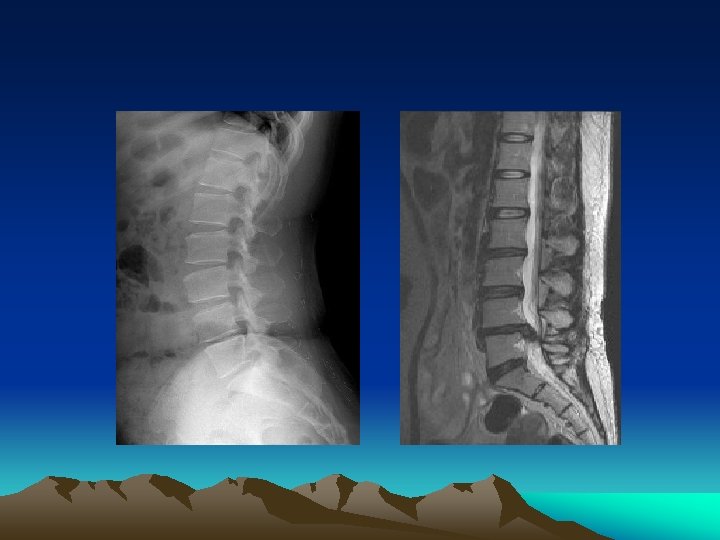

MRI appearance • T-2 weighted image • Black disc – dessication

Imaging • Plain Radiography limited to patients with: -findings suggestive of systemic disease -trauma • Failure to improve after 4 to 6 weeks • CT and MRI more sensitive for cancer and infections – also reveal herniation and stenosis • Reserve for suspected malignancy, infection or persistent neurologic defecit

MRI • The gold standard for imaging of the herniated lumbar disc is magnetic resonance imaging